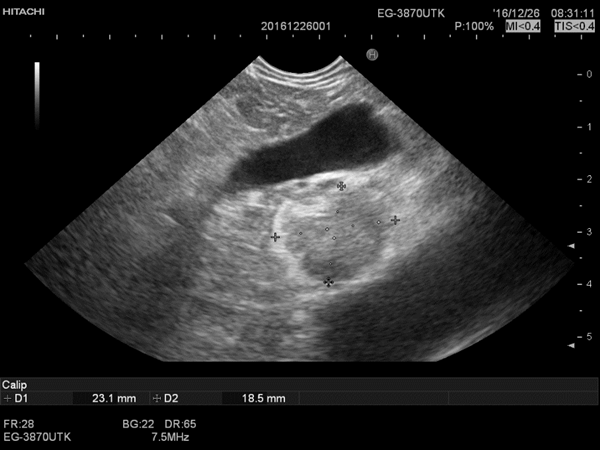

该患者曾在多家医院辗转就诊,因其存在与低血糖不相适应的胰岛素水平异常而被怀疑为胰岛素瘤,但常规腹部B超及胰腺CT均未见明显瘤体。1年来,患者时刻警惕低血糖症状发作,夜间需要维持补充葡萄糖,生活痛苦。万般无奈下得知我院曾诊断过类似病例,遂至内分泌科就诊,荆爱玉教授复习患者既往的资料后与消化内科马师洋主治医师沟通,决定安排患者行超声胃镜检查。2016年12月20日在超声内镜检查中发现患者胰腺头部近钩突紧邻门静脉有一1.8x0.8cm肿瘤,高度符合胰岛素瘤特点。

2016.12.22.行FNA穿刺活检与无水乙醇消融术,将穿刺针准确刺入。病变内留取样本送检,超声监控下注射无水乙醇1.6ml。